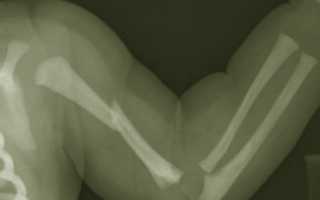

Перелом плечевой кости

Плечевая кость – это длинная кость верхней конечности, в которой анатомически выделяют тело (диафиз) и два конца (эпифизы). Около 7% всех переломов в травматологии занимает перелом плечевой кости и главной причиной являются удары и падения. Все эти травмы относятся к разновидностям перелома руки.

Какие бывают виды переломов плеча и плечевых костей

В зависимости от повреждения того или иного отдела плечевой кости, выделяют следующие виды переломов:

- Перелом в проксимальном отделе,который, в свою очередь, подразделяется на внутрисуставный (перелом головки и анатомической шейки плечевого сустава) и внесуставный (перелом бугорка плечевой кости и перелом хирургической шейки).

- Перелом диафиза плеча(различают перелом верхней, средней или нижней трети).

- Перелом в дистальном отделе.

Различают надмыщелковый и перелом мыщелков (чрезмыщелковый, Т- и У-образный межмыщелковый и изолированный перелом мыщелков)

В большинстве случаев наблюдается перелом верхнего конца плеча в районе хирургической шейки, а также прелом в области средней трети плеча и в месте расположения надмыщелков в нижней трети. В результате бытовой травмы чаще всего наступает закрытый перелом плечевой кости, не сопровождающийся повреждением кожи. Такие переломы лечатся проще всего и, зачастую, не вызывают осложнений.